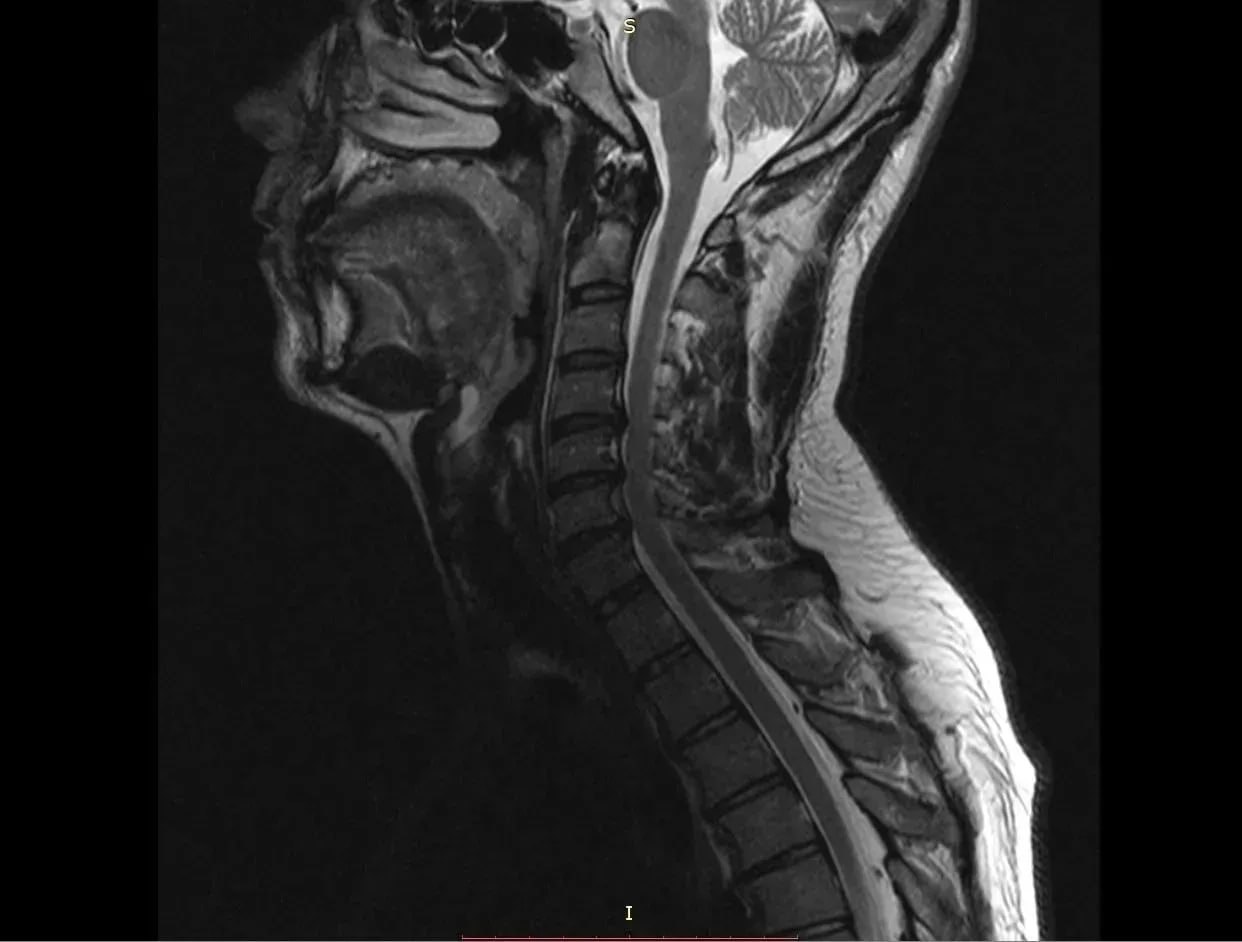

38-летний мужчина долгое время страдал от остеохондроза шейного отдела позвоночника. С августа 2025 года боль усилилась и распространилась на правую руку. Вместе с болью пришли слабость и онемение. Он обратился в БСМП №1, где ему поставили диагноз – диско-остеофитный стеноз позвоночного канала. Это значит, что на уровне ряда шейных позвонков произошло сужение, а находящиеся в позвоночном канале структуры подверглись сдавливанию.

Нейрохирурги устранили стеноз позвоночного канала и стабилизировали позвоночник, одновременно укрепив его разными титановыми конструкциями. Через три часа после операции пациент уже мог вставать на ноги. Боль пошла на спад, в мышцы вернулись силы. Мужчину выписали на пятые сутки после операции. Однако его еще ждет лечение в отделении реабилитации.